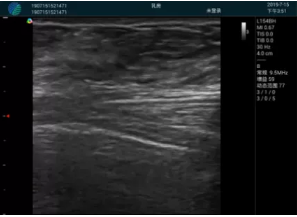

可視化穿刺引導(dǎo)

M20實時引導(dǎo):向包塊后方間隙注射利多卡因